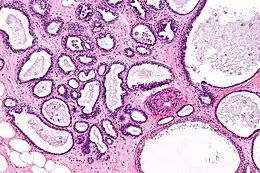

Description de cette image, également commentée ci-après

Histologie de la mastopathie kystique diffuse

La mastose ou mastopathie kystique diffuse est un terme qui englobe un certain nombre de lésions histologiques bénignes non cancéreuses et non inflammatoires.